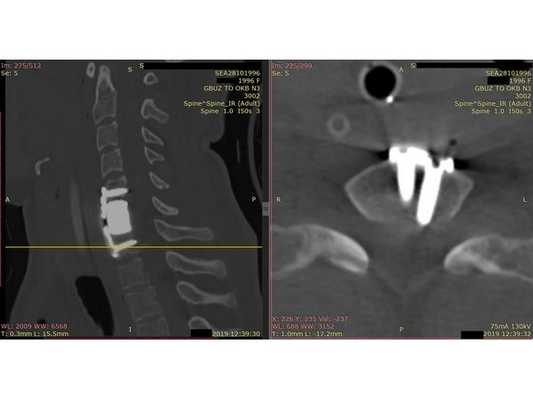

- Компьютерная томография шейного отдела позвоночника: выявлен компрессионно-оскольчатый перелом тела 6-го шейного позвонка (С6) и его дуги справа.

Контрольная КТ шейного отдела позвоночника на уровне тела позвонка С6. Виден установленный кейдж из пористого никелида титана и фиксирующая шейная пластина.

- Сформировали имплант из пористого никелида титана и установили между телами позвонков С5 и С7.

- Установили шейную пластину и зафиксировали 4 винтами: по 2 винта в тела позвонков С5 и С7. Выполнили рентген для контроля.